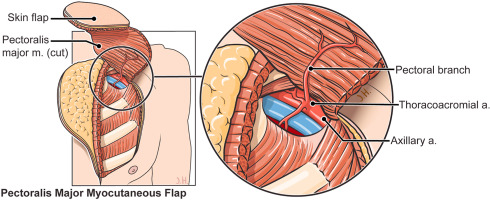

Flaps

Local and regional flap surgeries are performed to restore complex tissue defects. These procedures preserve blood supply, enhance healing, and improve functional and cosmetic results. Ideal for trauma, cancer reconstruction, and chronic wounds.